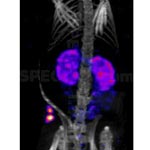

O metal é empregado como catalisador no craqueamento do petróleo nas refinarias, e em diversos processos químicos como alquilação, hidrogenação e polimerização. Também usado enquanto Oxiortosilicato de Lutécio para activar cintilador de Cério em camera gama de última geração, na medicina nuclear.